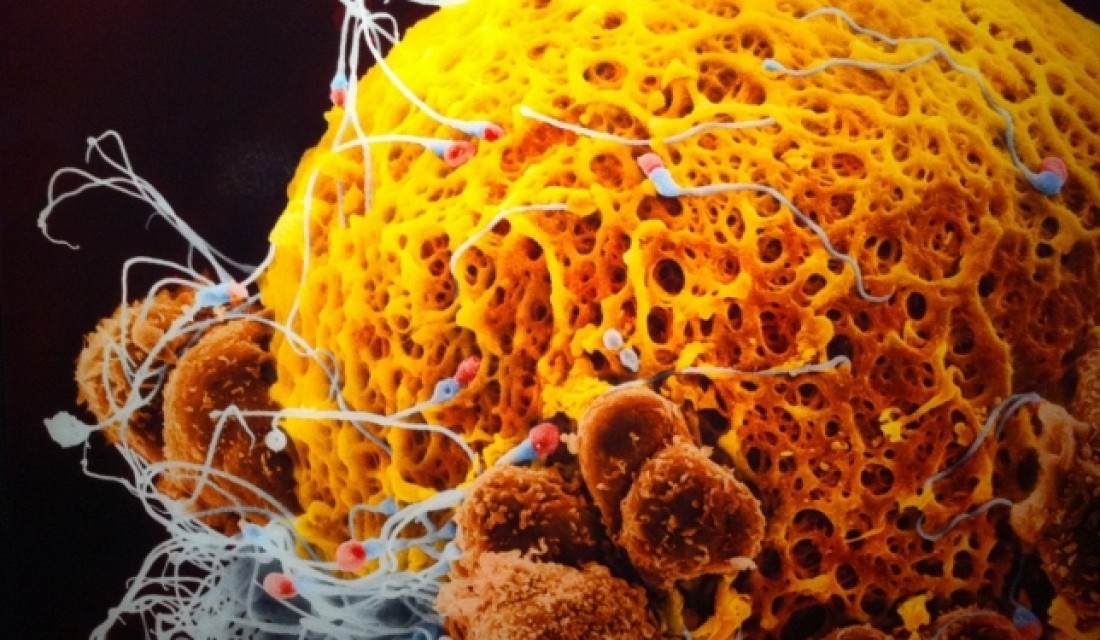

Միլիոնավոր սպերմատոզոիդներ շարժվում են դեպի արգանդի վզիկը:

Ձվաբջիջը և սպերմատոզոիդները